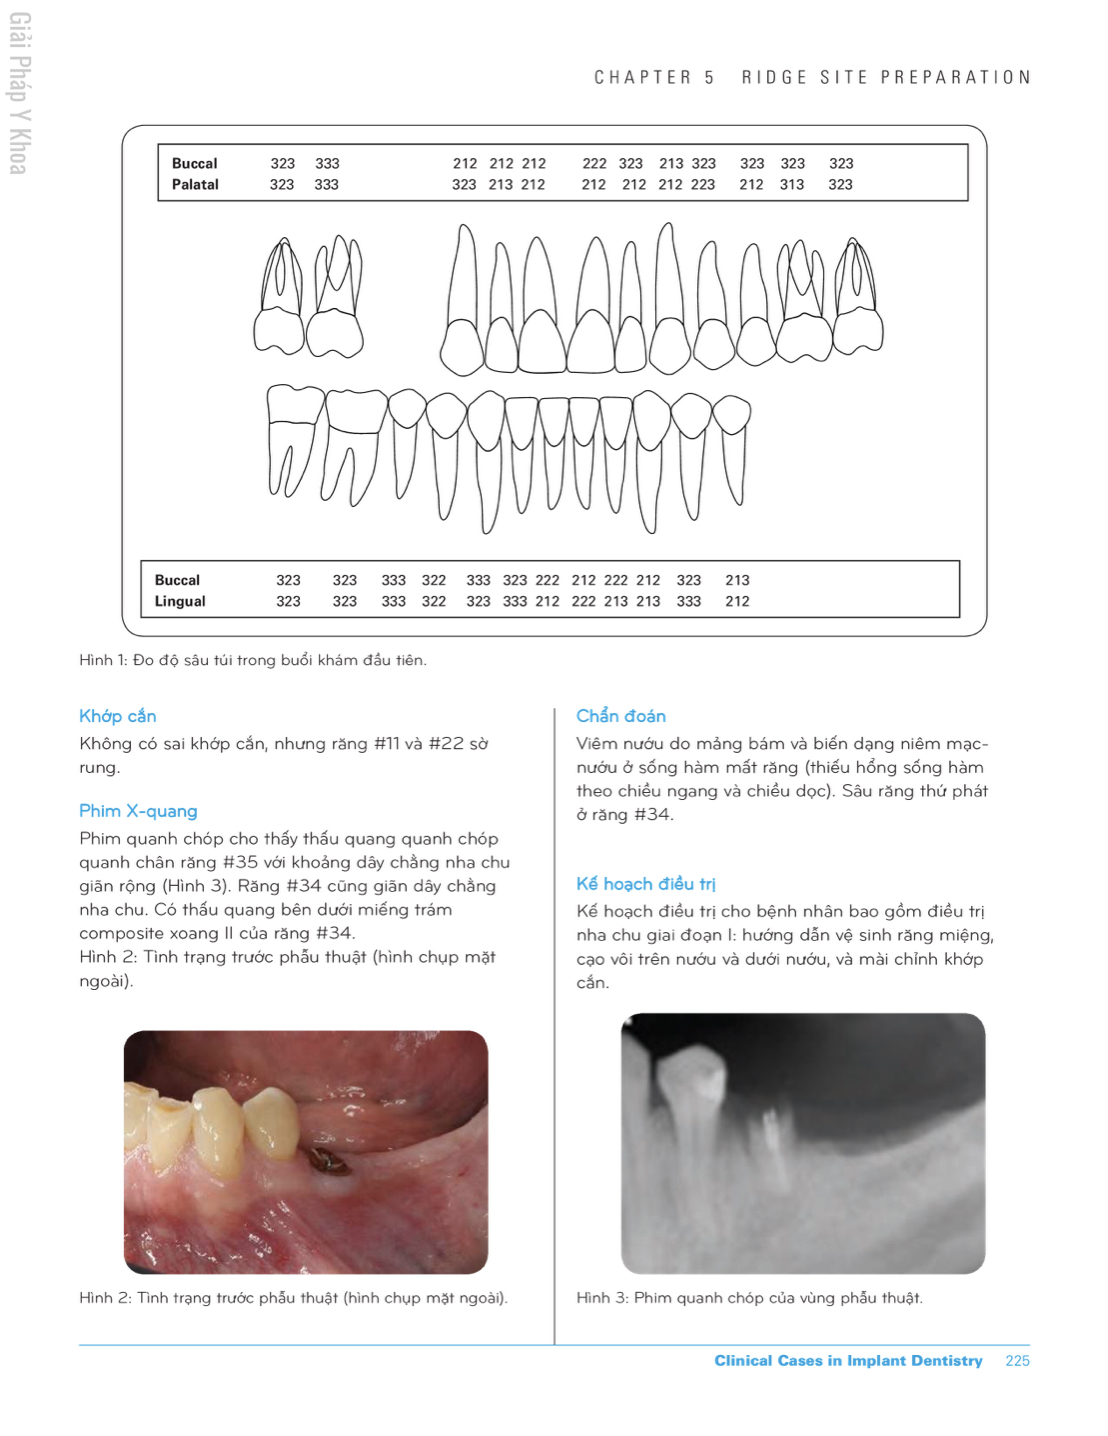

Các ca lâm sàng trong Implant chỉnh nha